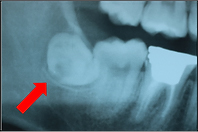

下の写真は、親知らずが横向きに生えていて隙間があります。

下の写真は、その隙間に食べかすが入ってしまっています。

この隙間は下の方が深歯ブラシが届かず、このままでは親知らずと手前の歯が2本とも虫歯になってしまうので抜いたほうが良いケースです。